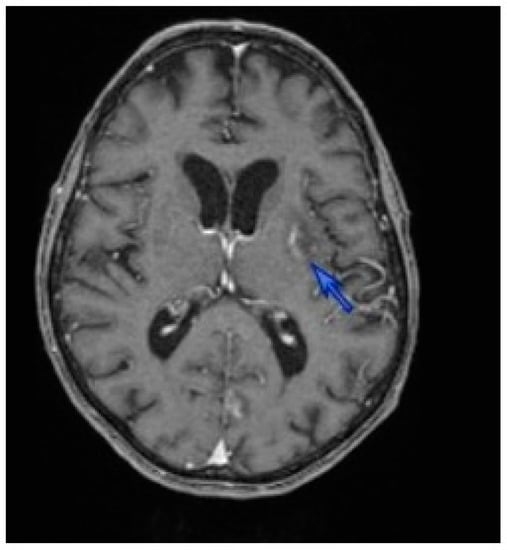

In October 2013, a 51-year-old man from South France was hospitalized for 40 kg weight loss caused by a dysphagia due to an oral candidiasis and herpes over the previous four months. He presented with general weakness, fever, productive cough and dyspnea with normal oxygen saturation. He had been diagnosed HIV positive in 2003. For three years, he showed a poor compliance with anti-HIV treatment. There was no history of travel abroad. Laboratory test results showed: 0.51 Giga/L lymphocytopenia with 6 CD4 + T cells/mm3; 70.7 mg/L C-reactive protein (CRP) level (N < 10); 681 U/L lactate dehydrogenase (LDH) level (N 100–620); 6.85 mg/L beta 2 micro globulin (N 1.09–2.53) level; and HIV viral load higher than 500,000 copies/mL. Toxoplasma serology tested positive, showing an acquired immunity profile (positive IgG and negative IgM antibodies) since 2010. Hepatitis C serology showed a past infection profile. Both computed tomography (CT) and positron emission tomography (PET) scans showed micro-cysts and bilateral diffuse ground-glass opacities in the lungs, and a single-characteristic cerebral toxoplasmosis lesion of the left capsular area (Figure 1). The microscopic examination of Diff Quick and Toluidin Blue-stained bronchoalveolar lavage (BAL) specimen showed Toxoplasma gondii tachyzoites, and both trophic and asci forms of Pneumocystis jirovecii. T. gondii and P. jirovecii identification was confirmed by PCR assays targeting the rep-529 gene and 18S rRNA, respectively [7,8]. BAL tested negative for mycobacteria, fungi and CMV. The final diagnosis was pulmonary toxoplasmosis and Pneumocystis pneumonia associated with cerebral toxoplasmosis in a patient with HIV-associated immunosuppression.

Figure 1. Computer tomography (CT) brain showing a 23 nm lenticular lesion in the left basal ganglia (blue arrow).